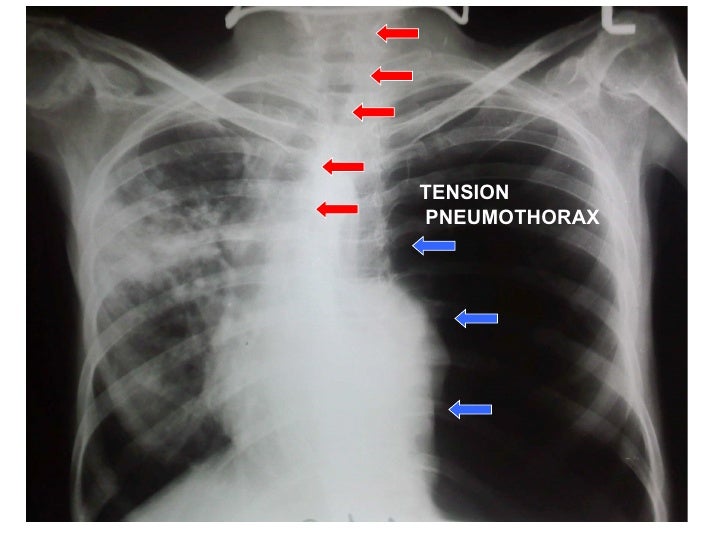

Pleural effusion wikipedia, the free. Also try. Pleural disorders medlineplus national library. Feb 16, 2011 cxr pneumothorax / pleural thickening 1. Prof.Dr.K.H.Noorul ameen’s unit m6 dr.G arun kumar image of the week 2. ≪ul><li>30 year old male came to opd. Pleural effusion causes, symptoms, and treatment webmd. Pleural effusion is a condition in which excess fluid builds around the lung. Learn more from webmd about different types of pleural effusions, and their symptoms. What are pleurisy and other pleural disorders? Nhlbi, nih. Other pleural disorders pneumothorax. Air or gas can build up in the pleural space. Pleurisy and other pleural disorders can be serious, depending on their causes. Imaging of pleural plaques, thickening, and tumors uptodate. Imaging procedures are commonly used in the diagnostic evaluation of pleural abnormalities. The imaging of pleural plaques, diffuse pleural thickening, and pleural.